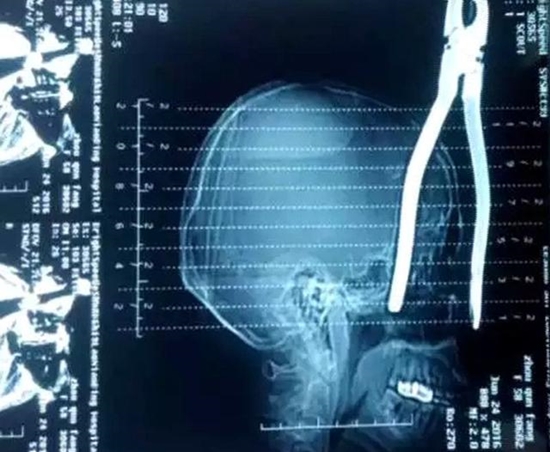

เมื่อวันที่ 27 มิถุนายน 2559 เว็บไซต์เซี่ยงไฮ้อิสต์ รายงานอุบัติเหตุชวนสยองที่เป็นอุทาหรณ์แก่คนเดินใกล้ตึกสูงได้เป็นอย่างดี เมื่อหญิงชาวจีนรายหนึ่งถูกคีมปากจระเข้ที่ร่วงจากอพาร์ตเมนต์ 31 ชั้น ปักคาศีรษะอย่างน่าหวาดกลัว ลึกกว่า 15 เซนติเมตร ศัลยแพทย์ต้องใช้เวลากว่า 14 ชั่วโมงในการผ่าตัดนำคีมเจ้ากรรมออกจากศีรษะเธอได้

รายงานระบุว่า ด้ามจับคีมได้ปักลงไปลึกกว่า 15 เซนติเมตรในศีรษะของเธอ ทำให้แพทย์ต้องดำเนินการผ่าตัดโดยใช้เวลากว่า 14 ชั่วโมงกว่าจะนำคีมออกมาได้ อย่างไรก็ดีเธอยังคงอยู่ในภาวะหมดสติอยู่ตอนนี้ แพทย์เผยว่ามีความเสี่ยงสูงมากที่จะติดเชื้อ เพราะคีมดังกล่าวสกปรกและแผลของเธอก็ลึกเกินกว่าจะทำความสะอาดได้ ต้องดูแลเธออย่างใกล้ชิดไปอีกหลายสัปดาห์